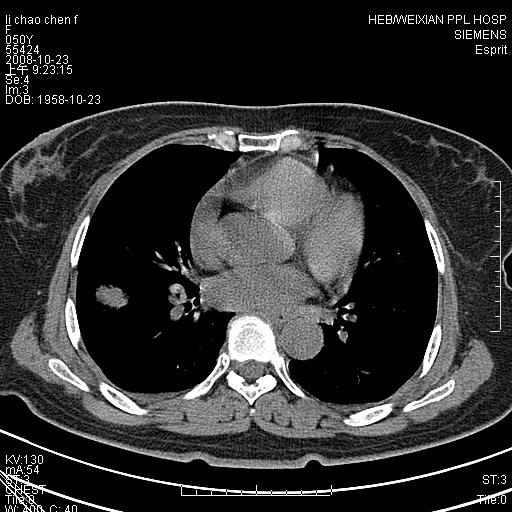

强化扫描后病灶几乎无增强,强化后的病灶看起来密度虽高,是我为了清晰改变了窗宽窗位。(有点弄巧呈拙)

提几点建议:第一,资料并未上传完整.缺少纵隔窗观察.第二,病灶须薄层观察其细微的征象.此点很重要.第三.尽量强化检查,帮助明确.

我认为必须有纵隔窗资料;且最好做增强ct检查。现在发言为时过早***